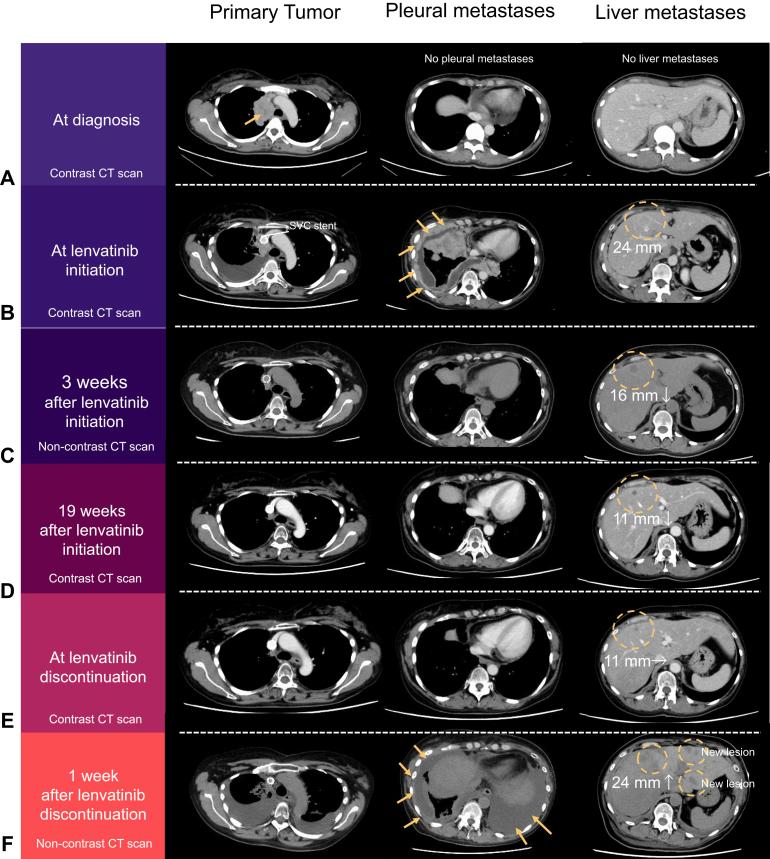

Rapid Response to Lenvatinib and Disease Flare After Discontinuation in a Patient With Thymic Carcinoma Harboring KIT Exon 11 Mutation: A Case Report.

Lenvatinib, a multitarget tyrosine kinase inhibitor for c-Kit and other kinases, has exhibited promising efficacy in treating advanced or metastatic thymic carcinoma (TC). Here, we present the case of a patient with metastatic TC harboring a exon 11 deletion and amplification. The patient exhibited a remarkable response to lenvatinib but experienced rapid disease progression after discontinuation of lenvatinib, referred to as a "disease flare." This case report indicates that mutations and amplification can predict lenvatinib response in patients with TC. However, in such cases, there might be a risk of disease flares after lenvatinib discontinuation.

乐伐替尼是一种针对c-Kit和其他激酶的多靶点酪氨酸激酶抑制剂,在治疗晚期或转移性胸腺癌(TC)方面已显示出有前景的疗效。在此,我们报告一例患有转移性胸腺癌且存在第11外显子缺失和扩增的患者病例。该患者对乐伐替尼表现出显著反应,但在停用乐伐替尼后疾病迅速进展,即所谓的“疾病爆发”。本病例报告表明,突变和扩增可预测胸腺癌患者对乐伐替尼的反应。然而,在这类病例中,停用乐伐替尼后可能存在疾病爆发的风险。